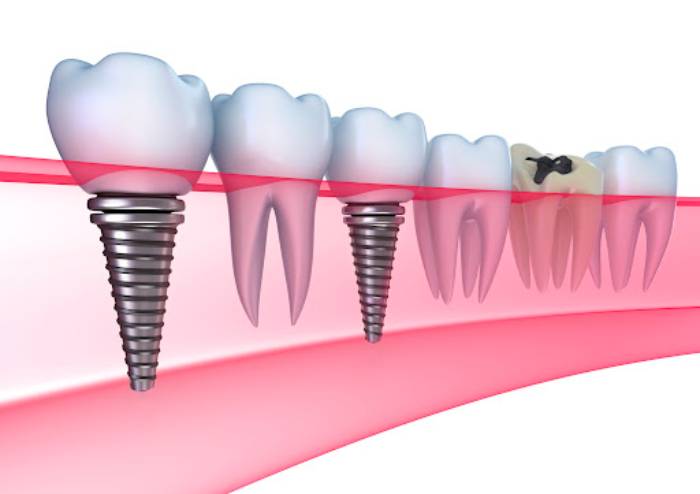

1- ایمپلنت دندانی

ایمپلنت دندان یکی از پیشرفتهترین و مؤثرترین روشهای جایگزینی دندانهای از دست رفته است که در آن یک پایه فلزی (عموماً از تیتانیوم) بهطور دائمی در استخوان فک قرار میگیرد و پس از جوش خوردن به استخوان، یک روکش دندانی بر روی آن نصب میشود. این روش بهعنوان یک گزینه دائمی و طبیعی برای بازسازی دندانهای از دست رفته شناخته میشود و مزایای زیادی دارد.

انواع ایمپلنت دندانی:

- ایمپلنت تکدندانی: این نوع ایمپلنت برای جایگزینی یک دندان از دست رفته استفاده میشود. یک پایه ایمپلنت به استخوان فک قرار میگیرد و روکش دندانی به آن متصل میشود.

- ایمپلنتهای چندگانه (بریج ایمپلنت): این روش برای جایگزینی چند دندان از دست رفته بهطور همزمان استفاده میشود. در این روش، ایمپلنتها بهعنوان پایهای برای پل دندانی عمل میکنند.

- ایمپلنت فوری (Immediate Implant): در این روش، ایمپلنت بلافاصله پس از کشیدن دندان در محل خالی قرار میگیرد. این روش برای کسانی که به دنبال یک راهحل سریع هستند، مناسب است.

- ایمپلنتهای All-on-4 یا All-on-6: این روش برای افرادی که نیاز به جایگزینی کامل یک ردیف دندان دارند استفاده میشود. در این روش، تنها با استفاده از 4 یا 6 ایمپلنت، یک ردیف کامل دندان جایگزین میشود.

- ایمپلنتهای زیرکشی (Subperiosteal Implant): این نوع ایمپلنت برای افرادی که حجم کافی استخوان فک ندارند استفاده میشود و ایمپلنت در زیر لثه و روی استخوان فک قرار میگیرد.

ایمپلنت دندانی بهعنوان یک گزینه دائمی و مؤثر برای جایگزینی دندانهای از دست رفته میتواند بسیاری از مشکلات دندانی را حل کند و کیفیت زندگی فرد را بهطور قابل توجهی بهبود بخشد.